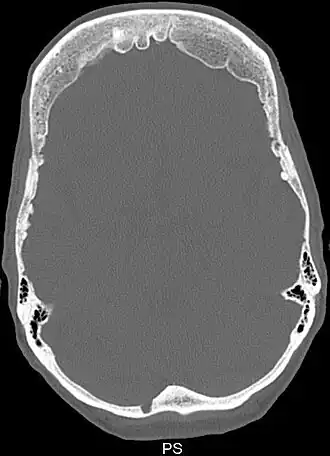

Снимок компьютерной томографии черепа пациента с гиперостозом лобной кости

Синдром Морганьи — Стюарта — Мореля (метаболическая краниопатия) — состояние, связанное с широким спектром эндокринных проблем, включая сахарный и несахарный диабеты и гиперпаратиреоз[1]. Другие признаки и симптомы включают головную боль, головокружение, избыточное оволосение по мужскому типу, проблемы с менструацией, галакторею, ожирение, депрессию и эпилептические припадки[1][2]. Утолщение внутренней поверхности лобной части черепа является, как правило, начальной стадией заболевания, известного как hyperostosis frontalis interna[1][3].

Диагноз ставят на основе жалоб и клинической картины; также используют гистологические методы исследования. На рентгенограмме визуализируется утолщение лобной кости. Синдром Морганьи — Стюарта — Мореля дифференцируют в первую очередь от болезни Иценко — Кушинга и адипозогенитальной дистрофии.